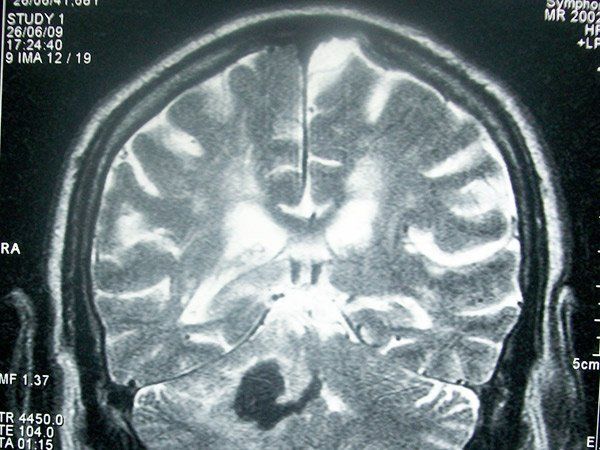

La EVC se produce debido a la obstrucción del abastecimiento de sangre y oxígeno al cerebro, lo que provoca una pérdida rápida de las funciones cerebrales.

Esta obstrucción puede ser causada por un bloqueo o por una hemorragia y el resultado de la falta de oxígeno en el cerebro puede conducir a severas discapacidades o inclusoa la muerte.